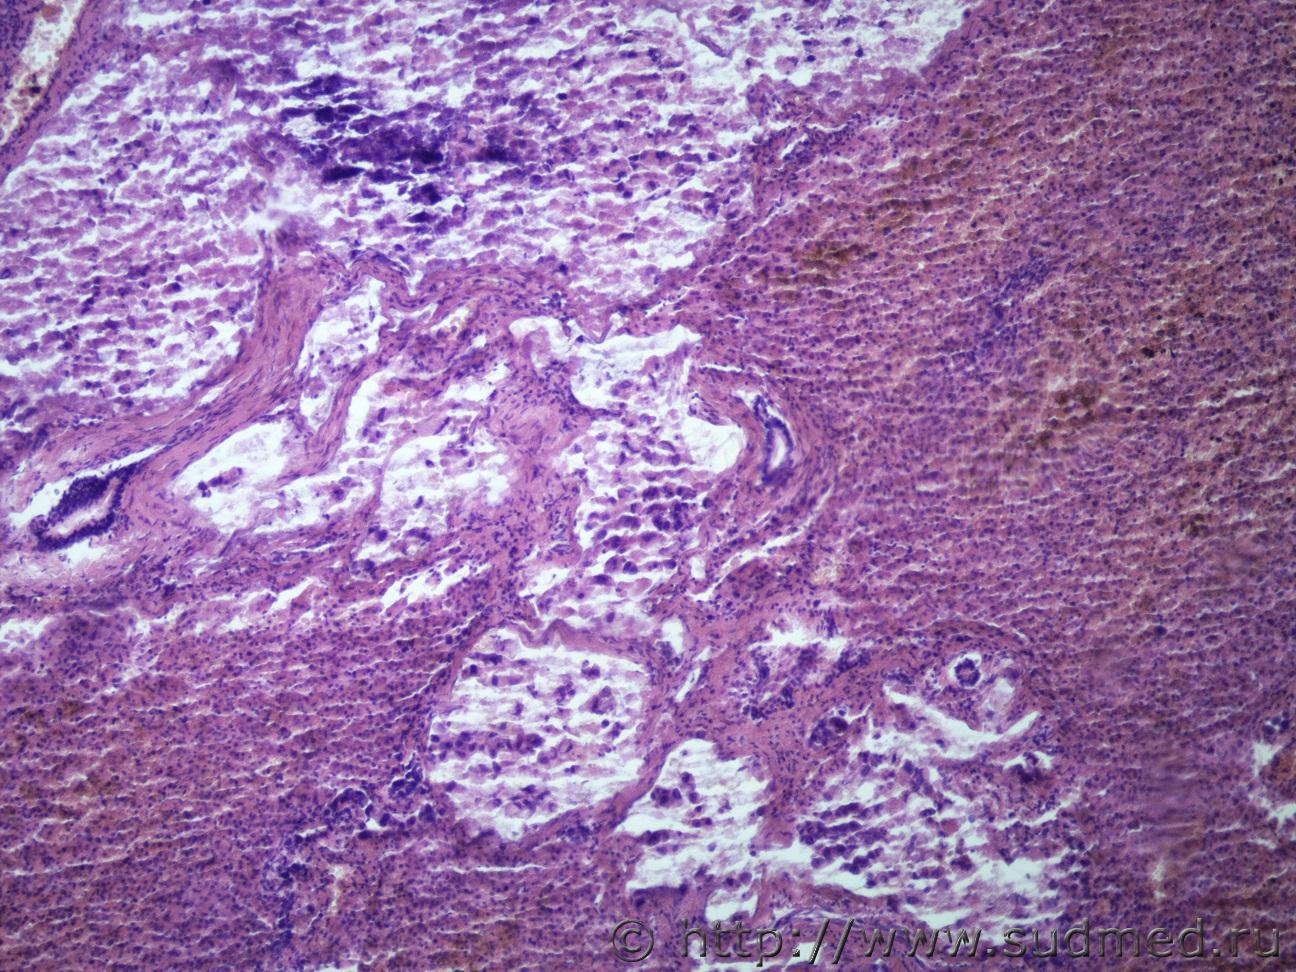

Ув. коллеги. Жен 60 лет. Образование в желудке и в печени. Материал взят не очень удачно, в желудке нечего нет. А в печени опухоль. Перстневидные клетки есть, но не много, местами озера слизи. Могу ли я в данном случая по метастазу поставить рак. Судебная медицина - Прикрепленное изображениеСудебная медицина - Прикрепленное изображениеСудебная медицина - Прикрепленное изображениеСудебная медицина - Прикрепленное изображение

Перстневидноклеточный рак.

Коллоидный( слизистый рак) , либо аденкарцинома с перстневидноклеточным типом.